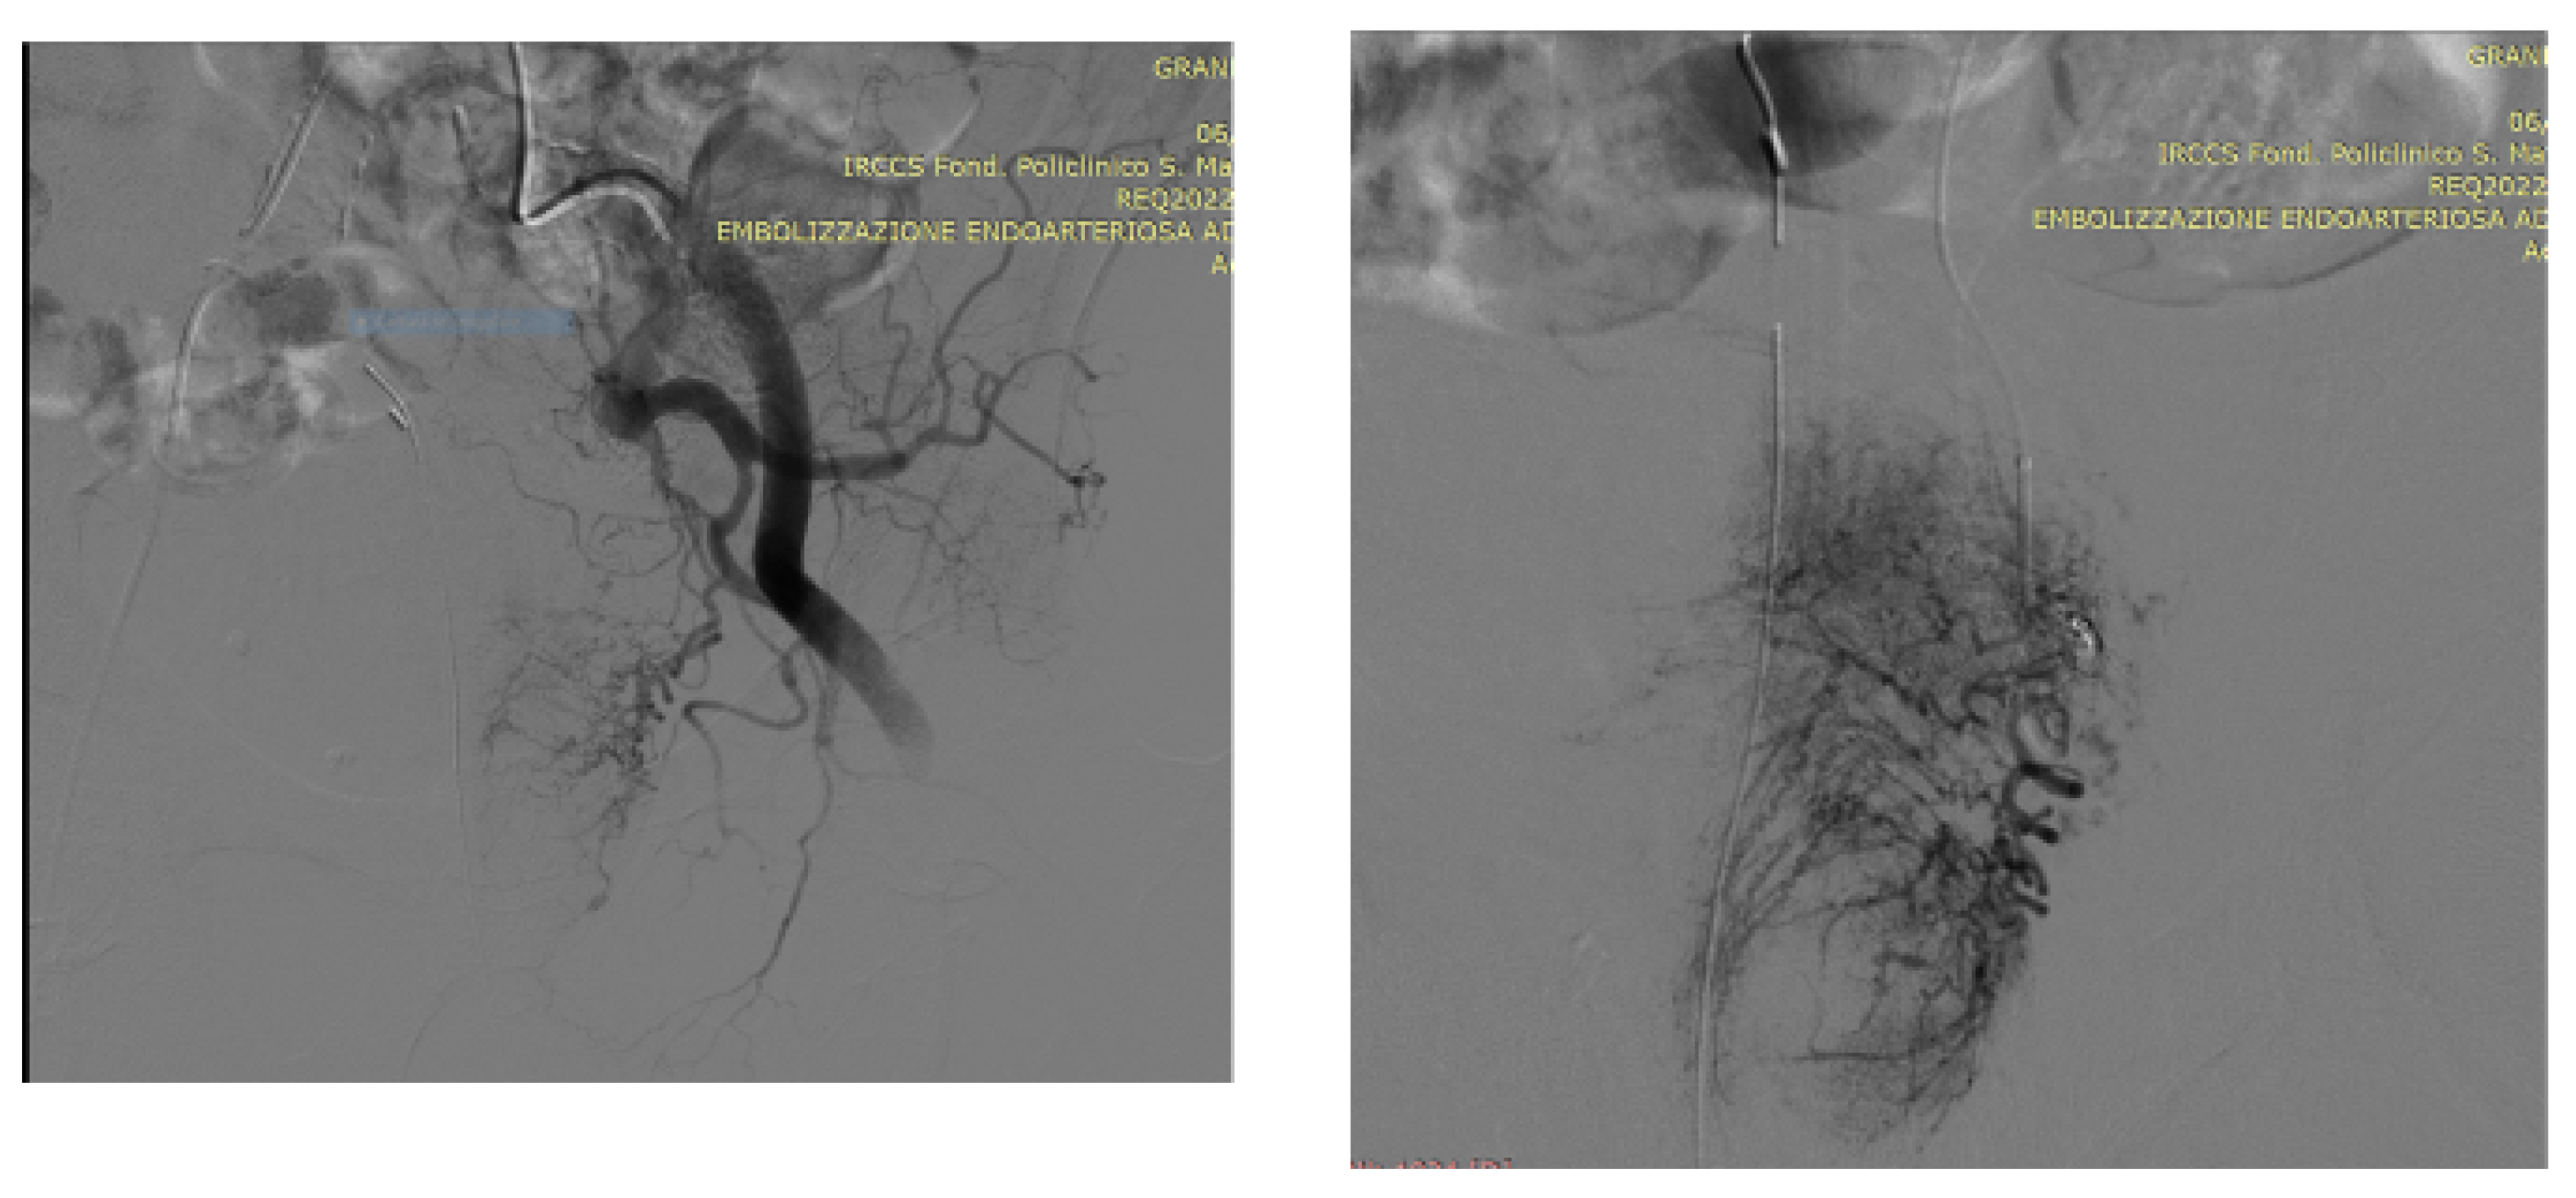

Technical Details of PAE